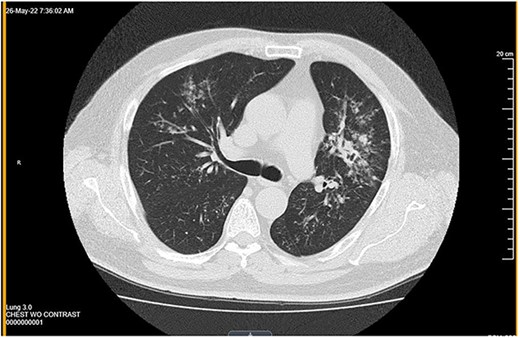

Neck ultrasound demonstrated an enlarged right-sided with a nodule (measuring 3.58 × 4.12 cm) and two left-sided nodules measuring 1.1 and 1.4 cm in size (Fig. 1a and b). The ultrasound also showed a 1 cm nodule inferior to the left lobe, suspicious of a parathyroid adenoma or enlarged lymph node. CT chest revealed multiple nodules in the left pulmonary parenchyma (Fig. 2). Flexible laryngoscopy revealed normal bilateral vocal cord movement but severe inflammation and swelling of the larynx. Subsequent FNA of both the right and left thyroid nodules showed benign results.

Computed tomography showed multiple nodules in the left pulmonary parenchyma.